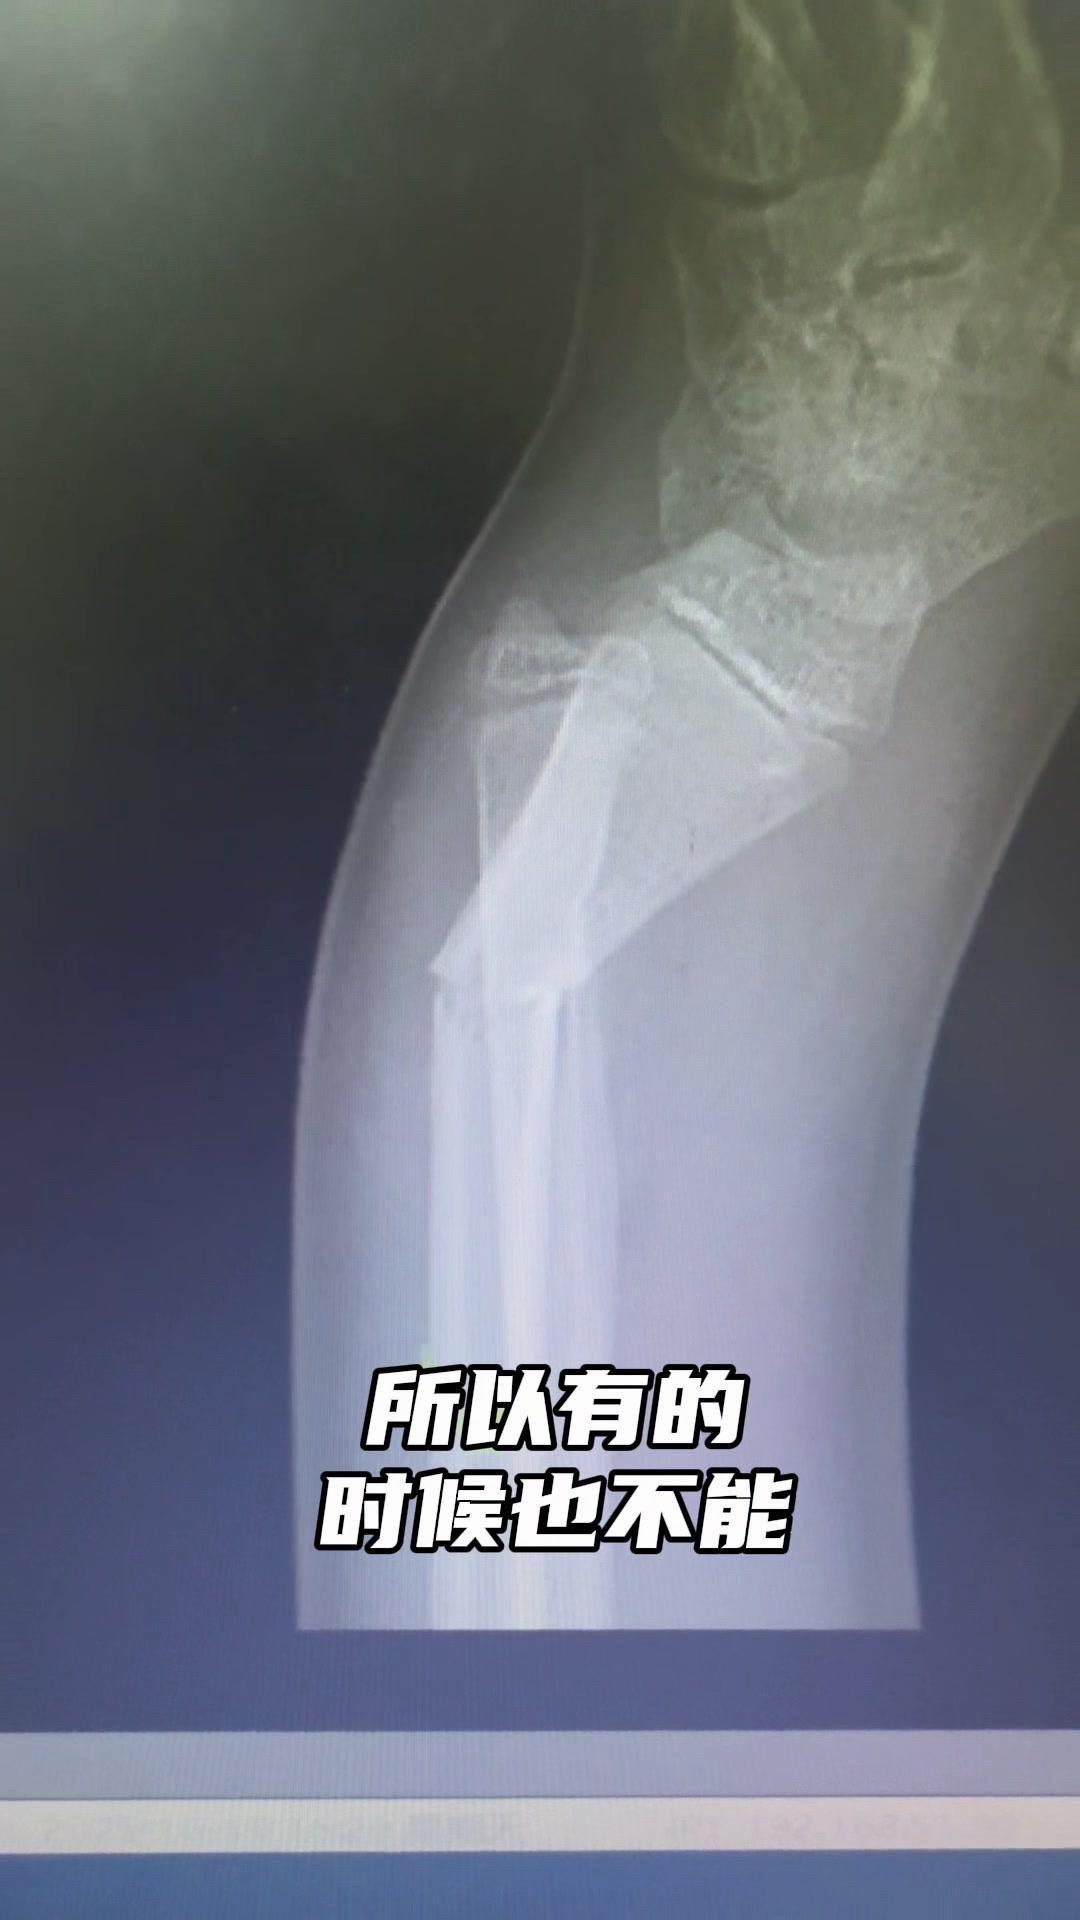

儿童骨折别拖延!💡上周接诊一个10岁女孩,摔了一跤后腕部疼痛还伴有畸形,家长觉得是小伤没在意,结果一周后孩子疼得更厉害,畸形也更明显了。来医院拍片一看,妥妥的骨折,而且才一周就开始出现模糊骨痂,掌区还有45度左右的成角畸形。家长这才意识到问题严重性,其实孩子受伤后出现疼痛、畸形,哪怕看起来不严重,也得及时检查,别让小问题拖成大麻烦。